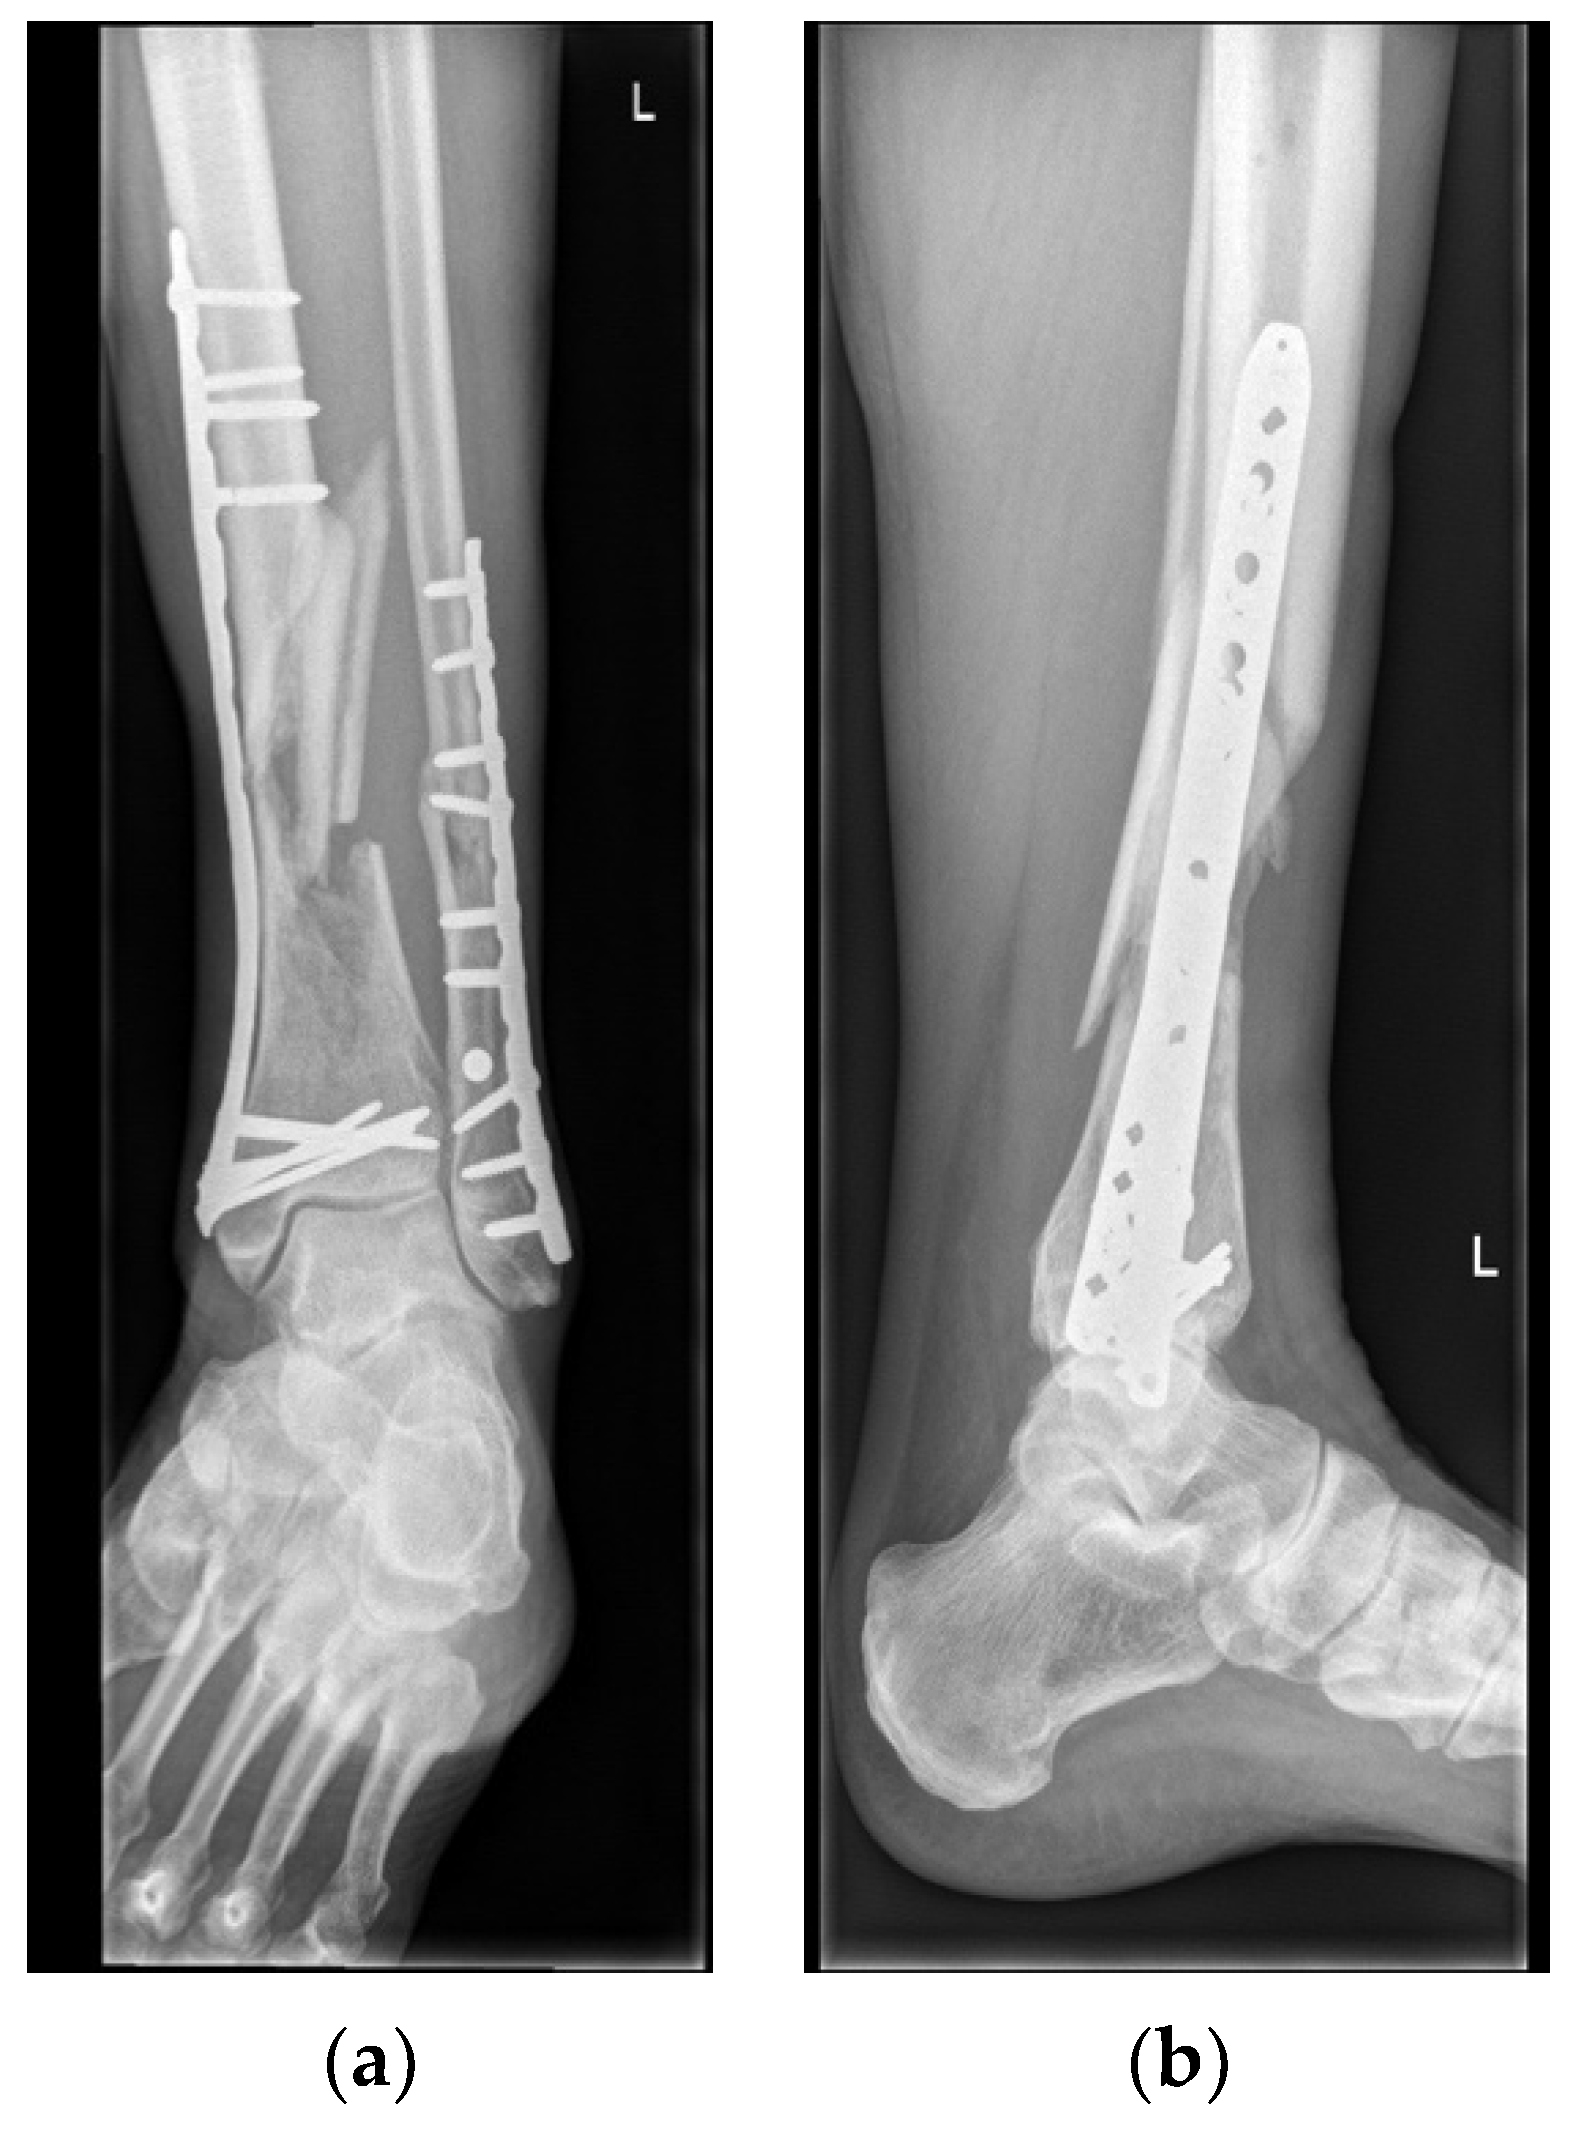

Surgical Procedures